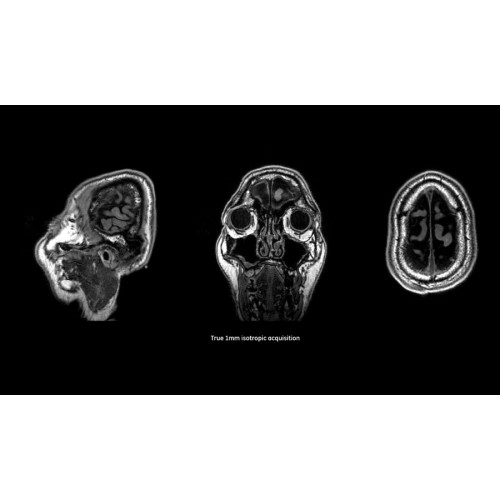

Детализация изображений

Система SIGNA Pioneer воплощает поразительные достижения в области визуализации. Передовая технология Total Digital Imaging (TDI) позволяет добиться большей четкости изображений и на четверть повысить соотношение сигнал/шум.

TDI построена на трех базовых компонентах:

• Технология Direct Digital Interface (DDI) использует независимый аналого-цифровой преобразователь для оцифровки сигнала от каждого из 97 радиочастотных каналов, что обеспечивает значительное увеличение качества за счет уменьшения фонового шума.

• Технология Digital Micro Switching (DMS) — это следующее поколение технологий радиочастотных катушек, основанное на замене аналоговых схем блокировки сверхбыстрыми микропереключателями (MEMS), что делает возможным быстрое переключение катушек для дальнейшего расширения возможностей визуализации с нулевым TE.

• Технология Digital Surround Technology (DST) — это новая технология объемной оцифровки данных, объединяющая сигналы от каждого элемента катушки. Прекрасное соотношение сигнал/шум и чувствительность поверхностных катушек в сочетании с превосходной однородностью и высокой проникающей способностью встроенной радиочастотной катушки — все это позволяет создавать качественные изображения не только позвоночника, но и всего тела.

Помимо технологии 97 РЧ-каналов, SIGNA Pioneer использует магнит 3.0Т высокой однородности, предназначенный для повышения качества визуализации во всех областях, а также закладывающий прочный фундамент для долгосрочных инвестиций и роста клинических возможностей.